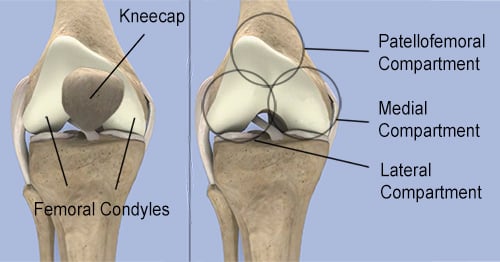

Knee joint anatomy

The knee joint is composed of three bones: The femur (thighbone), the patella (kneecap) and the tibia (shinbone). Two knob-like protuberances on the bottom of the femur known as the femoral condyles make up the top of the knee. The upper portion of the tibia known, as the tibial plateau, makes up the bottom. The kneecap rests in front of the femoral condyles.

There are three compartments of the knee, each named for its relationship to these portions of bone:

- The medial (inner) compartment of the knee.

- The lateral (outer) compartment is formed by the articulation (or joining) of the lowest part of the thighbone (femur) and the highest part of the shinbone (the tibia).

- The patellofemoral compartment, located where patella rests in front of the femur.

Arthritis of the knee may occur in any one of these compartments. However, the medial compartment is the most frequent site of knee osteoarthritis, followed by the lateral compartment. (Arthritis that is confined to the patellofemoral compartment of the knee is rare and may require a patellofemoral joint replacement.)